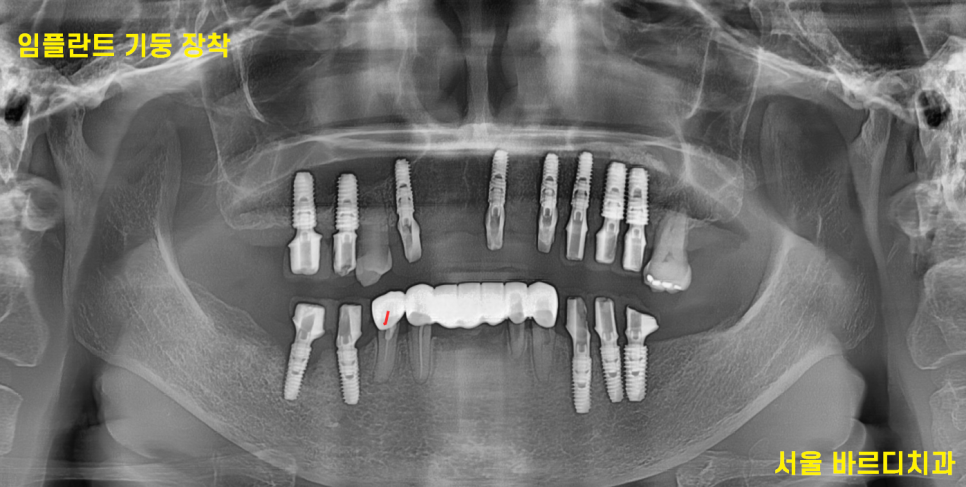

< 보철 인상채득>

231222

시간이 흘러 보철 제작을 위한 날이 되었습니다.

어금니가 없기 때문에 높이를

2단계에 걸쳐 회복해주고

240117

맞춤형 기둥을 사용

임플란트와 보철을 연결해주는 기둥을 제작하였습니다.

그리고 기둥 위에 보철을 끼워주면,,?